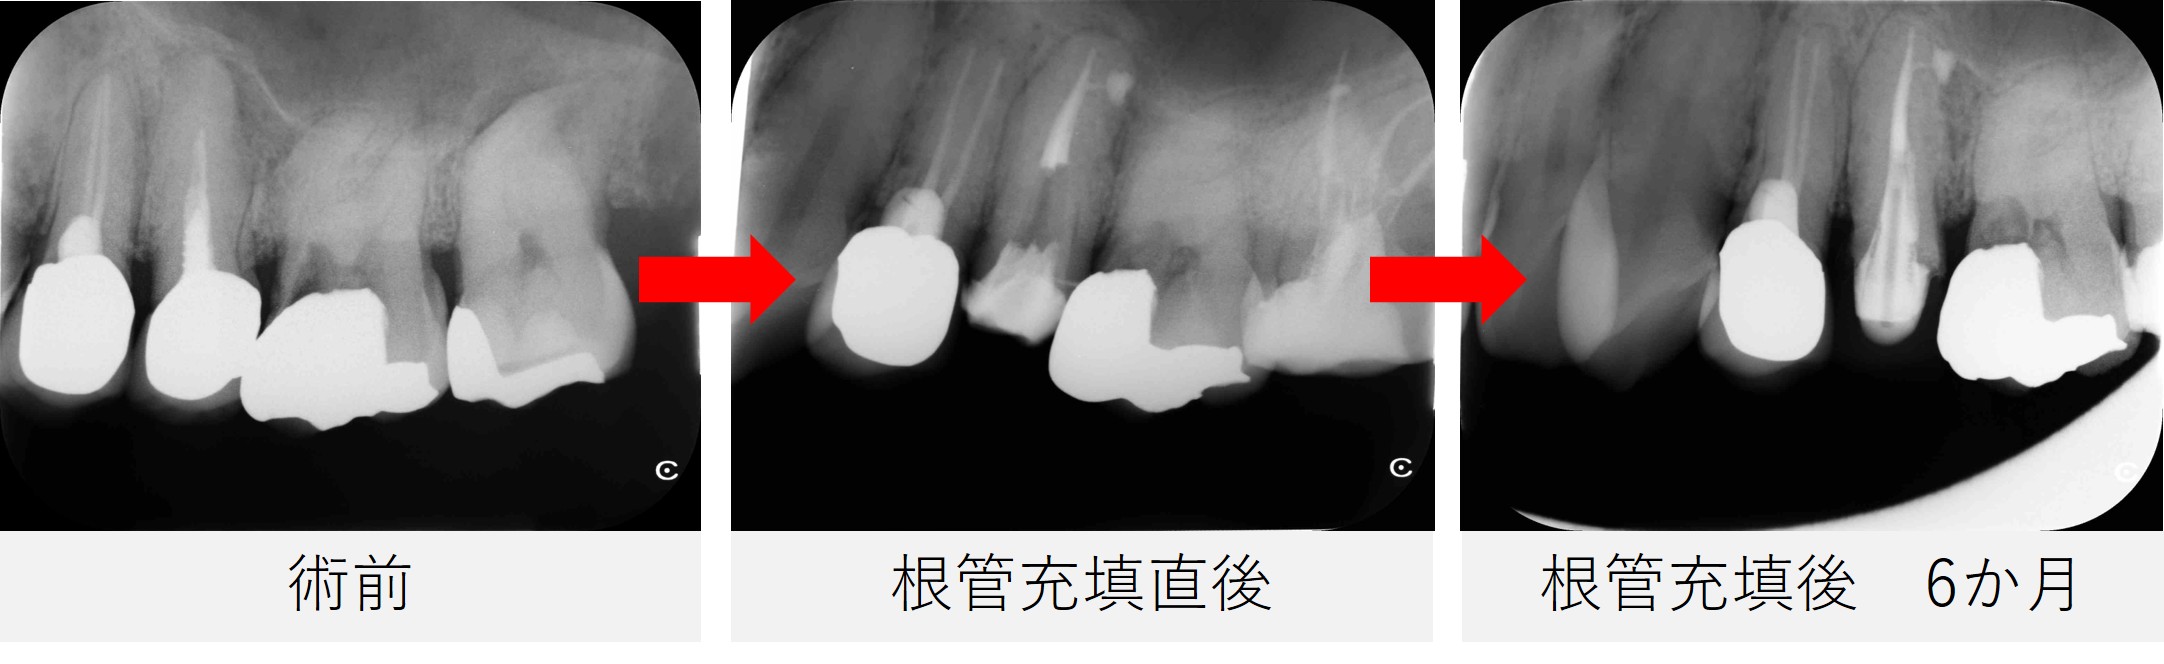

根管充填後は、症状の有無だけでなく、レントゲンやCT画像を用いて根の先や側面の骨の状態を確認しながら経過を観察していきます。

根の先に炎症があった場合、治療後すぐに骨が回復するわけではなく、徐々に改善していくことが多いためです。

そのため、定期的にレントゲン等の撮影を行い、根の先や側面の骨が回復してきているかを確認していきます。

根管充填後から6カ月

- 痛みはなく、鼻のにおいなどの症状も認められませんでした。

- レントゲンおよびCTで確認したところ、根の先や側面に見られていた透過像は縮小し、骨の回復傾向が確認されました。

- 特に、根の側面に見られていた透過像は、歯の根の途中から分かれている細い枝状の通路(側枝:そくし)に関連した炎症であった可能性が考えられます。

- 今回の症例では、根管治療後の経過観察でその透過像が縮小し、骨の回復傾向が確認されました。

- 炎症の改善がみられたため、最終補綴(被せ物の作製)へ移行する予定としました。